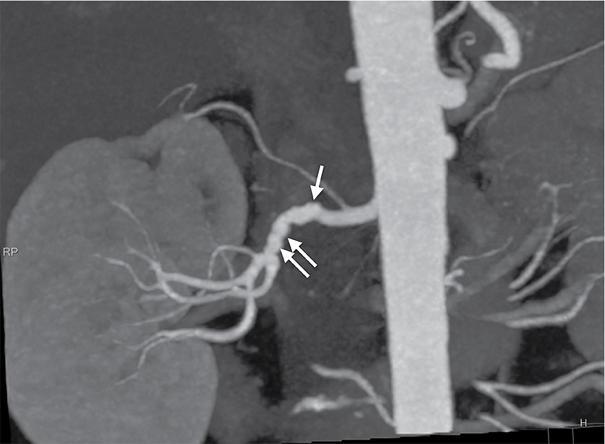

• CTA: It provides excellent spatial resolution of the abdominal aorta and entire renal arterial tree. RAS due to atherosclerosis is identified by presence of soft, calcific or mixed plaques in either eccentric or concentric distribution in proximal 2 cm with renal artery diameter reduction (Fig. 10.18.1.4A and B). RAS due to medial type of FMD appears as ‘string of beads’ pattern in mid and distal main renal artery with alternate areas of narrowing and dilatation (Fig. 10.18.1.5). CT signs of haemodynamically significant stenosis include poststenotic dilatation, renal parenchymal atrophy and reduced cortical enhancement. Sensitivity and specificity of CTA in diagnosing RAS is 96% and 99%, respectively.

Fig. 10.18.1.4 CT renal angiography images in maximum intensity projection (MIP) reconstructions in (A) axial and (B) coronal planes showing critical stenosis (arrows) of left renal artery at origin.

Fig. 10.18.1.5 MIP images of right renal artery in a case of fibromuscular dysplasia (FMD) showing ‘string of beads appearance’ as alternating areas of narrowing and dilatations (arrows).